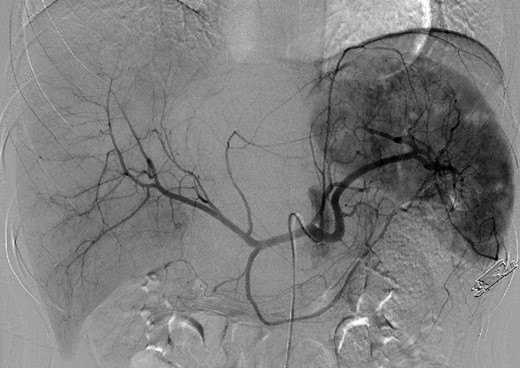

An 18-year-old woman presented with epigastric pain that started during a Japanese drum lesson. She was diagnosed with rupture of a hepatic tumor and transported to our hospital. She had no medical history of surgery, including abdominal surgery. Contrast-enhanced computed tomography (CT) revealed a 13-cm, low-density giant mass in the left hepatic lobe and high-density ascites, indicating abdominal bleeding from the liver tumor (Fig. 1). Ultrasonography confirmed a well-defined giant mass of the liver, comprising both cystic and solid lesions. Laboratory data showed a low hemoglobin level of 8.2 g/dl, and all the results of liver function tests and tumor marker measurement were within normal ranges. The patient underwent emergent celiac angiography, which revealed an avascular tumor with no evidence of extravasation from the hepatic artery. The left hepatic artery was considered to be the artery feeding the tumor and was embolized (Fig. 2). Magnetic resonance imaging (MRI) confirmed a well-defined giant multilocular lesion with fibrous partition (Fig. 3). After the patient's condition stabilized, she underwent left hepatic lobectomy. Laparotomy revealed bloody ascites and a large tumor in the left lobe of the liver; the right lobe appeared normal. The enlarged lymph nodes of the hepatoduodenal ligament were also dissected. Histological analysis of the resected specimen revealed a huge cystic mass of ∼12 × 9.5 cm. The mass was cystic and multilocular with a fibrous wall and filled with a massive blood clot (Fig. 4). The enlarged lymph node had a 25 × 23-mm cyst, which contained yellowish fluid. On microscopic examination, the wall of the cyst consisted of a tight elastic fiber meshwork composed of collagen fibers, which was accompanied by a small amount of acid mucopolysaccharide in the stroma and a lining of single-layered flat cells on the inner wall (Fig. 5a and b). Immunohistochemical staining revealed that the cyst wall was positive for both the endothelial marker CD31 and the lymphangial marker D2-40 (Fig. 5c and d). The cystic structure of the lymph node also was composed of elastic fiber components similar to those of the cyst in the liver and lined with single-layered flat cells, which were immunohistochemically positive both for CD31 and D2-40 (Fig. 5e). The pathological diagnosis was hepatic lymphangioma combined with lymphangioma of the lymph nodes. The patient's postoperative course was uneventful, and she was discharged on Day 8. During follow-up for almost 4 years since the surgical treatment, the patient has presented no sign of recurrence.

Emergent angiography demonstrated an avascular tumor and did not reveal any extravasation from the hepatic artery.